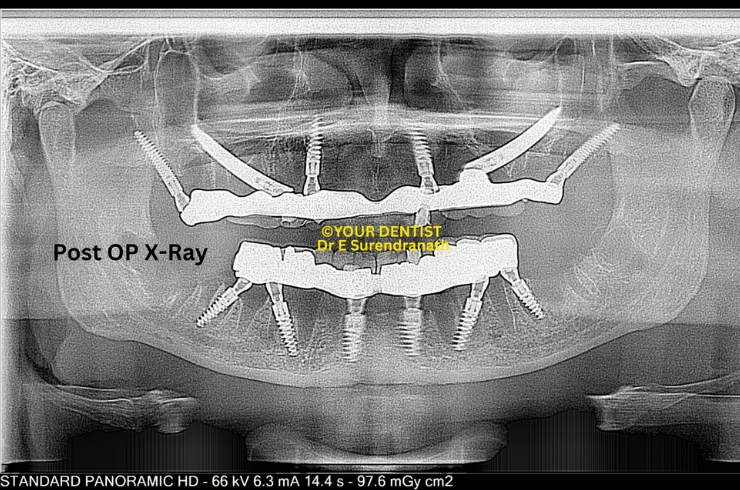

Patzi implant protocl - Pre OP Xray